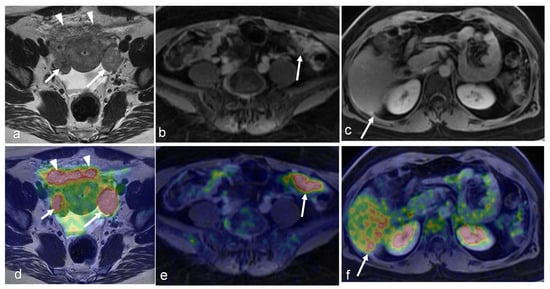

3.1. Cervical Cancer

3.2. Endometrial Cancer

3.3. Ovarian Cancer

3.4. Vaginal and Vulvar Cancers